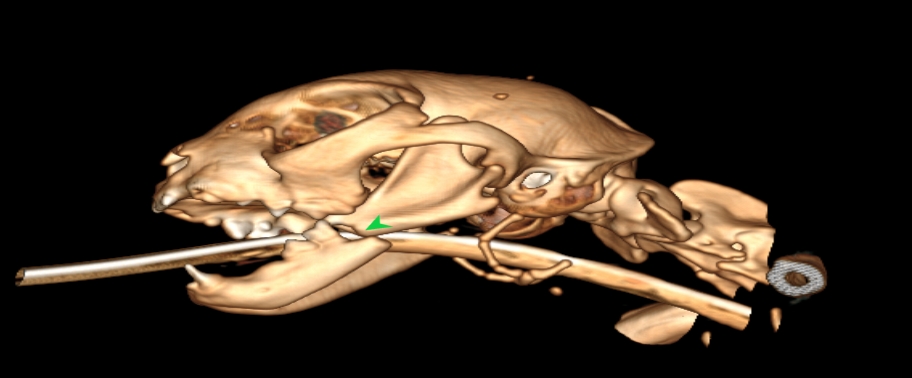

狗狗電腦斷層掃描 不明原因口腔出血 嚴重牙周病 口腔惡性腫瘤 鱗狀上皮細胞癌(Squamous cell carcinoma,SCC)

主訴嘴巴突然流血 口腔潰爛 左下顎腫脹 同時有嚴重牙周病 經由口腔採樣 電腦斷層掃描 確認為鱗狀上皮細胞癌(Squamous cell carcinoma,SCC)同時已經侵犯下顎骨。確診後經由外科醫師、腫瘤科醫師、電腦斷層影像科醫師共同擬定治療計畫後

,大範圍切除左下顎,經過一年追蹤,目前狗狗一切安好喔。

*康復後

*電腦斷層影像

貓咪 下顎骨骨折

頭骨結構較為複雜 頭骨骨折相對於四肢長骨骨折 不容易靠xray 完整評估術前需要靠電腦斷層影像檢查評估骨折狀況才能良好評估手術方式 提高成功率